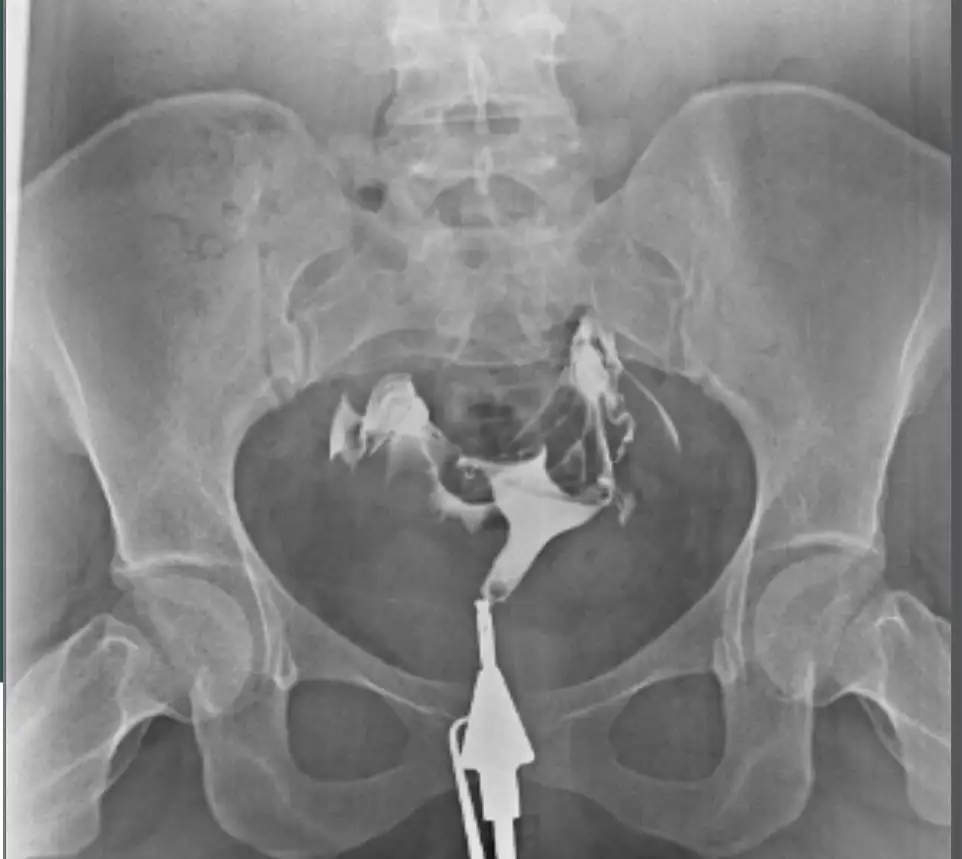

Banada çeken doktor hafif tıkanıklık vardı dedi tazikli ilaç verdim açıldı dedi.sonra klomen kullandım bende tek taraflı 2kist çıktı adet olamadım.çok kötü sancılanıyordum o sıralar 3 4 ayda anca geçti sonra doktorun ilgisini hiç beğenmedim başka doktora gittim oda senin dediğin gibi dedi hiç içine sinmemiş bir taraf açılmamış gibi tekrar yapabilirim dedi bende istemedim.o ay klomen ve çatlatma iğnesi oldum tekrar kist oluştu ondan sonra da bir daha doktora gitmedim.hep aynı şeyler klomen femera . çatlatma iğnesi bıktım artık .ne zaman klomen kullandıysam kist oluştu o yüzden oluruna bıraktım artık.bu ilaçlar bana gelmiyor demekkiCanım ben sana şöyle anlatayım benim 6 ay oldu cektireli haziranda çektirmiştim. O zaman kendi doktorumun olduğu hastanede cihaz bozuktu ne zaman yapılacağı da belli değildi. Doktora sordum başka yerde çektirip size getireyim mi diye o da olur zaman kaybetme ben kabul ederim dedi

Bende başka hastanede cektirdim çeken doktor hiç bi sıkıntı yok dedi

2 ay sonra kendi doktoruma gösterdim bi tüpünden ilaç yavaş geçmiş çeken doktor ne dedi dedi

Bende sorun yokmuş dedim benimde görmem lazım böyle emin olamıyorum dedi

Yani önce kabul ederim demişti şimdi benimde görmem lazım diyor 4 aydır ayni şeyi söylüyor hatta en son aşılama olmazsa isterim ama film dedi şimdi Bende napicam bilmiyorum ben o kağıdı ekliyorum şimdi

Ben 2 kere klomen 2 kere letu kullandım bende hiç kist olmadı ama zaten benim cikolata kistim var sağda. Hafif yavaş geçmiş dedigi de sol taraf. Kağıtta da açıldığına benzer bi yazı yazıyor zaten demekki doktor açmış yavaş geçse bile. Ki ben üstüne basa basa çeken doktora sordum tüpler de falan bisey var mı diye çünkü ilk kagidi aldım doktorda hayır hiç bisey yok tertemiz dedi. Görüntü var şimdi ekliyorumBanada çeken doktor hafif tıkanıklık vardı dedi tazikli ilaç verdim açıldı dedi.sonra klomen kullandım bende tek taraflı 2kist çıktı adet olamadım.çok kötü sancılanıyordum o sıralar 3 4 ayda anca geçti sonra doktorun ilgisini hiç beğenmedim başka doktora gittim oda senin dediğin gibi dedi hiç içine sinmemiş bir taraf açılmamış gibi tekrar yapabilirim dedi bende istemedim.o ay klomen ve çatlatma iğnesi oldum tekrar kist oluştu ondan sonra da bir daha doktora gitmedim.hep aynı şeyler klomen femera . çatlatma iğnesi bıktım artık .ne zaman klomen kullandıysam kist oluştu o yüzden oluruna bıraktım artık.bu ilaçlar bana gelmiyor demekki